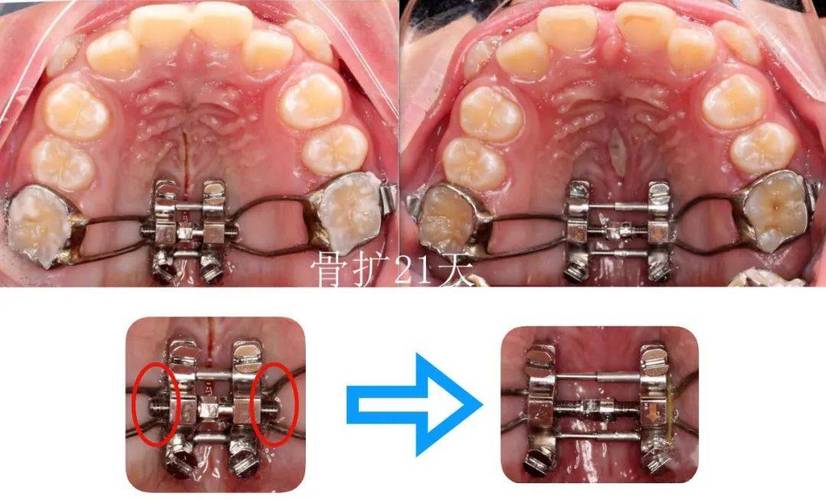

- 片段化:将传统全口弓丝拆分为独立或连接的片段,每个片段对应1-3颗目标牙齿,针对上颌前牙拥挤的片段弓,可能仅包含中切牙、侧切牙的托槽连接段,而磨牙区域保持独立,避免力量传导至非目标区域。

- 精准化:根据牙齿移动需求(如压低、伸长、扭转、内收/外展等),定制弓丝的形态、材质和尺寸,需压低单颗前牙时,片段弓可设计为“L形”,利用杠杆原理将力量集中在牙冠;需纠正扭转时,则通过弯制“转矩”角度,实现牙根的三维控制。

根据片段连接方式和功能,正畸片段弓可分为多种类型,不同类型适用于不同的牙齿问题,以下通过表格对比常见类型及其特点: